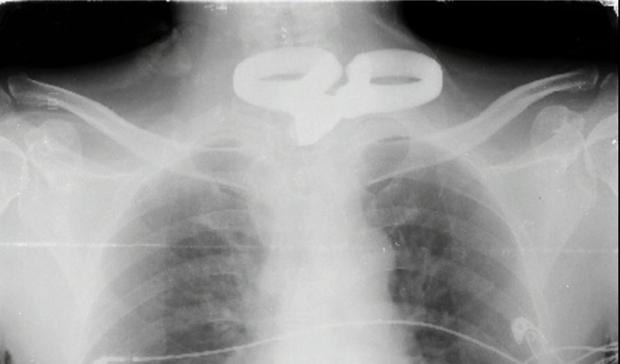

Khám phá câu chuyện đầy kỳ diệu về người đàn ông mù 2 mắt đã tự lấy kéo đâm vào bụng và ngực của mình, nhưng được cứu sống thông qua một ca phẫu thuật phức tạp và thành công tại Bệnh viện Đa khoa Trung ương Cần Thơ.

Người đàn ông mù 2 mắt tự lấy kéo đâm vào bụng và cổ - Ảnh 1.